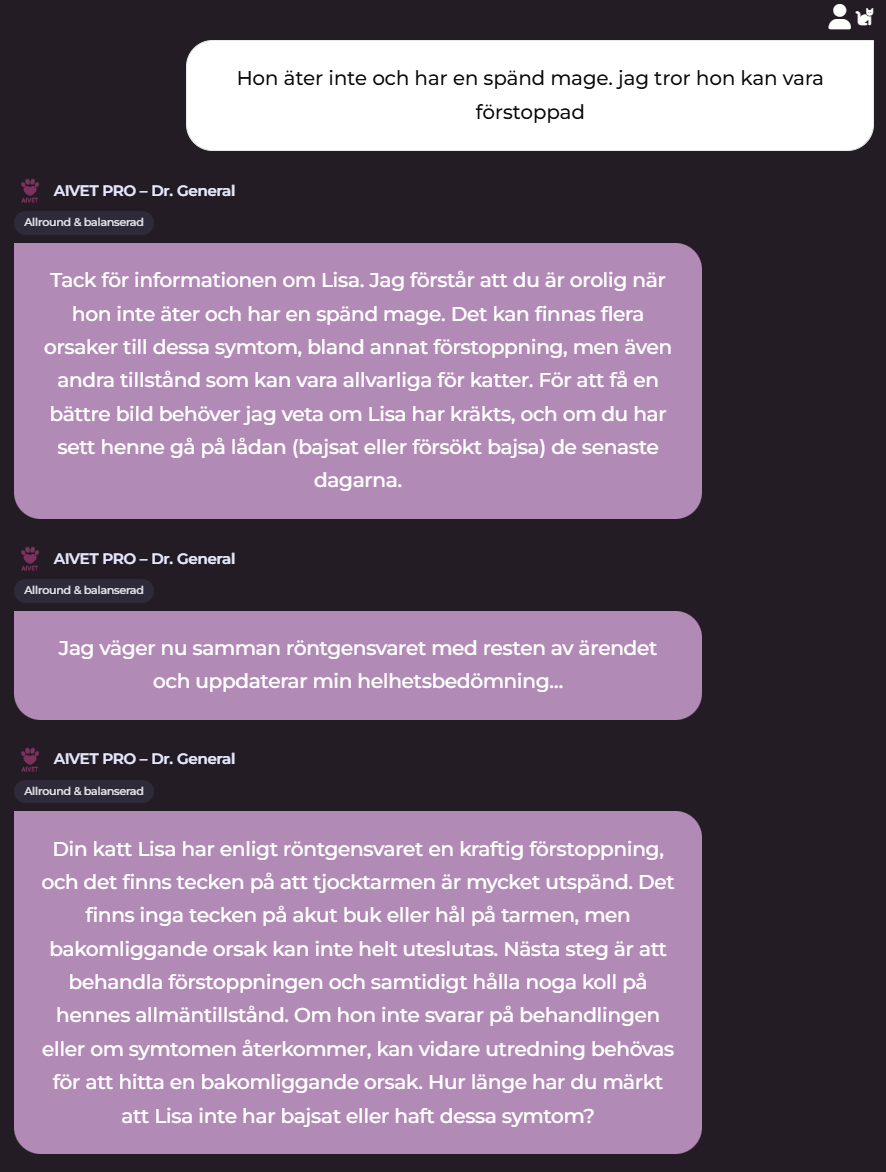

Radiologica Röntgentolk har utgått från chatt med din doktor som har en frågeställning som ska utredas. I detta exempel är det en katt som kan vara förstoppad. En komplett remiss har producerats. Remissens frågeställning tillsammans med röntgenbilder du kan ladda upp kommer att tolkas och generera ett remissvar.

I din huvudchatt så fortsätter ärendet kontinurligt och AI doktorn kan ställa nya frågor beroende på statusen i ditt ärende som t.ex resultatet från inkommande remissvar från Radiologica

I detta simulerade fall finns förslag på remiss, diagnos, rekomendation, akutläge etc i stetoskåpet.

Vi även lagt till att det faktiskt tas röntgenbilder baserat på remissen och AI-doktorns rekomendation baserat på denna. Detta sker självklart inte samtidigt i praktiken då djurägaren först måste komma in till kliniken och göra dessa föreslagna röntgenbilder.